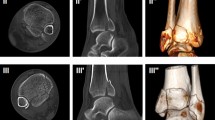

We analyzed the prevalence, location, dislocation, size, approximate volume, and distribution of ICFs within the three above mentioned CT-based classifications. The ICF was considered dislocated when there was displacement from the articular surface (Fig. 1). All CT scans were anonymized and saved as Digital Imaging and Communications in Medicine (DICOM) files. Four independent observers (levels of expertise: orthopedic and trauma surgery fellows and attending surgeons) reviewed the CT scans via the Picture Archiving and Communication System (PACS) to allow dynamic analysis of the complete CT dataset with coronal, sagittal, and axial planes.

The morphology was further assessed by measuring the maximum length and height in the sagittal and width in the axial CT planes (Fig. 1). An approximate ICF volume was calculated from those values.